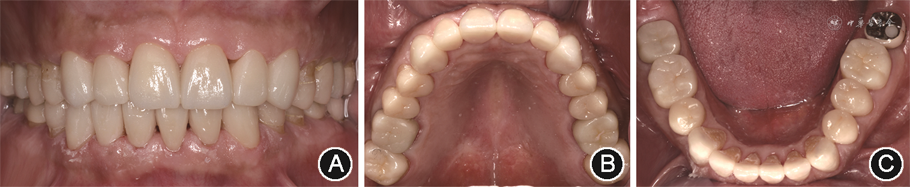

面像(5)最终修复:临时修复体戴用6个月后,复查美学与功能状态无异常,进行最终修复体的制作与粘接。综合微创、美观及不同部位强度的需求,修复体设计为17、16、13—23、26、27、37、36、46、47高透氧化锆单层瓷全冠修复;15、14、24、25、35、34、44二硅酸锂增强型玻璃陶瓷

贴面修复;33—43 二硅酸锂增强型玻璃陶瓷贴面修复。使用数字化口腔扫描设备复制经患者口内适应后的临时修复体形态,分阶段完成最终修复。修复即刻美学效果满意,21、22间龈乳头轻微退缩,患者唇齿关系协调,覆

覆盖正常,咬合稳定,前伸时后牙分离,侧方运动为尖牙保护

。考虑到患者有长期夜磨牙症病史,

力大,存在副功能运动,易发生修复体折裂和脱落,故修复完成即刻为患者制作厚度2.0 mm配戴于上颌的夜磨牙症软

垫,以期提高远期修复成功率[5](图9)。